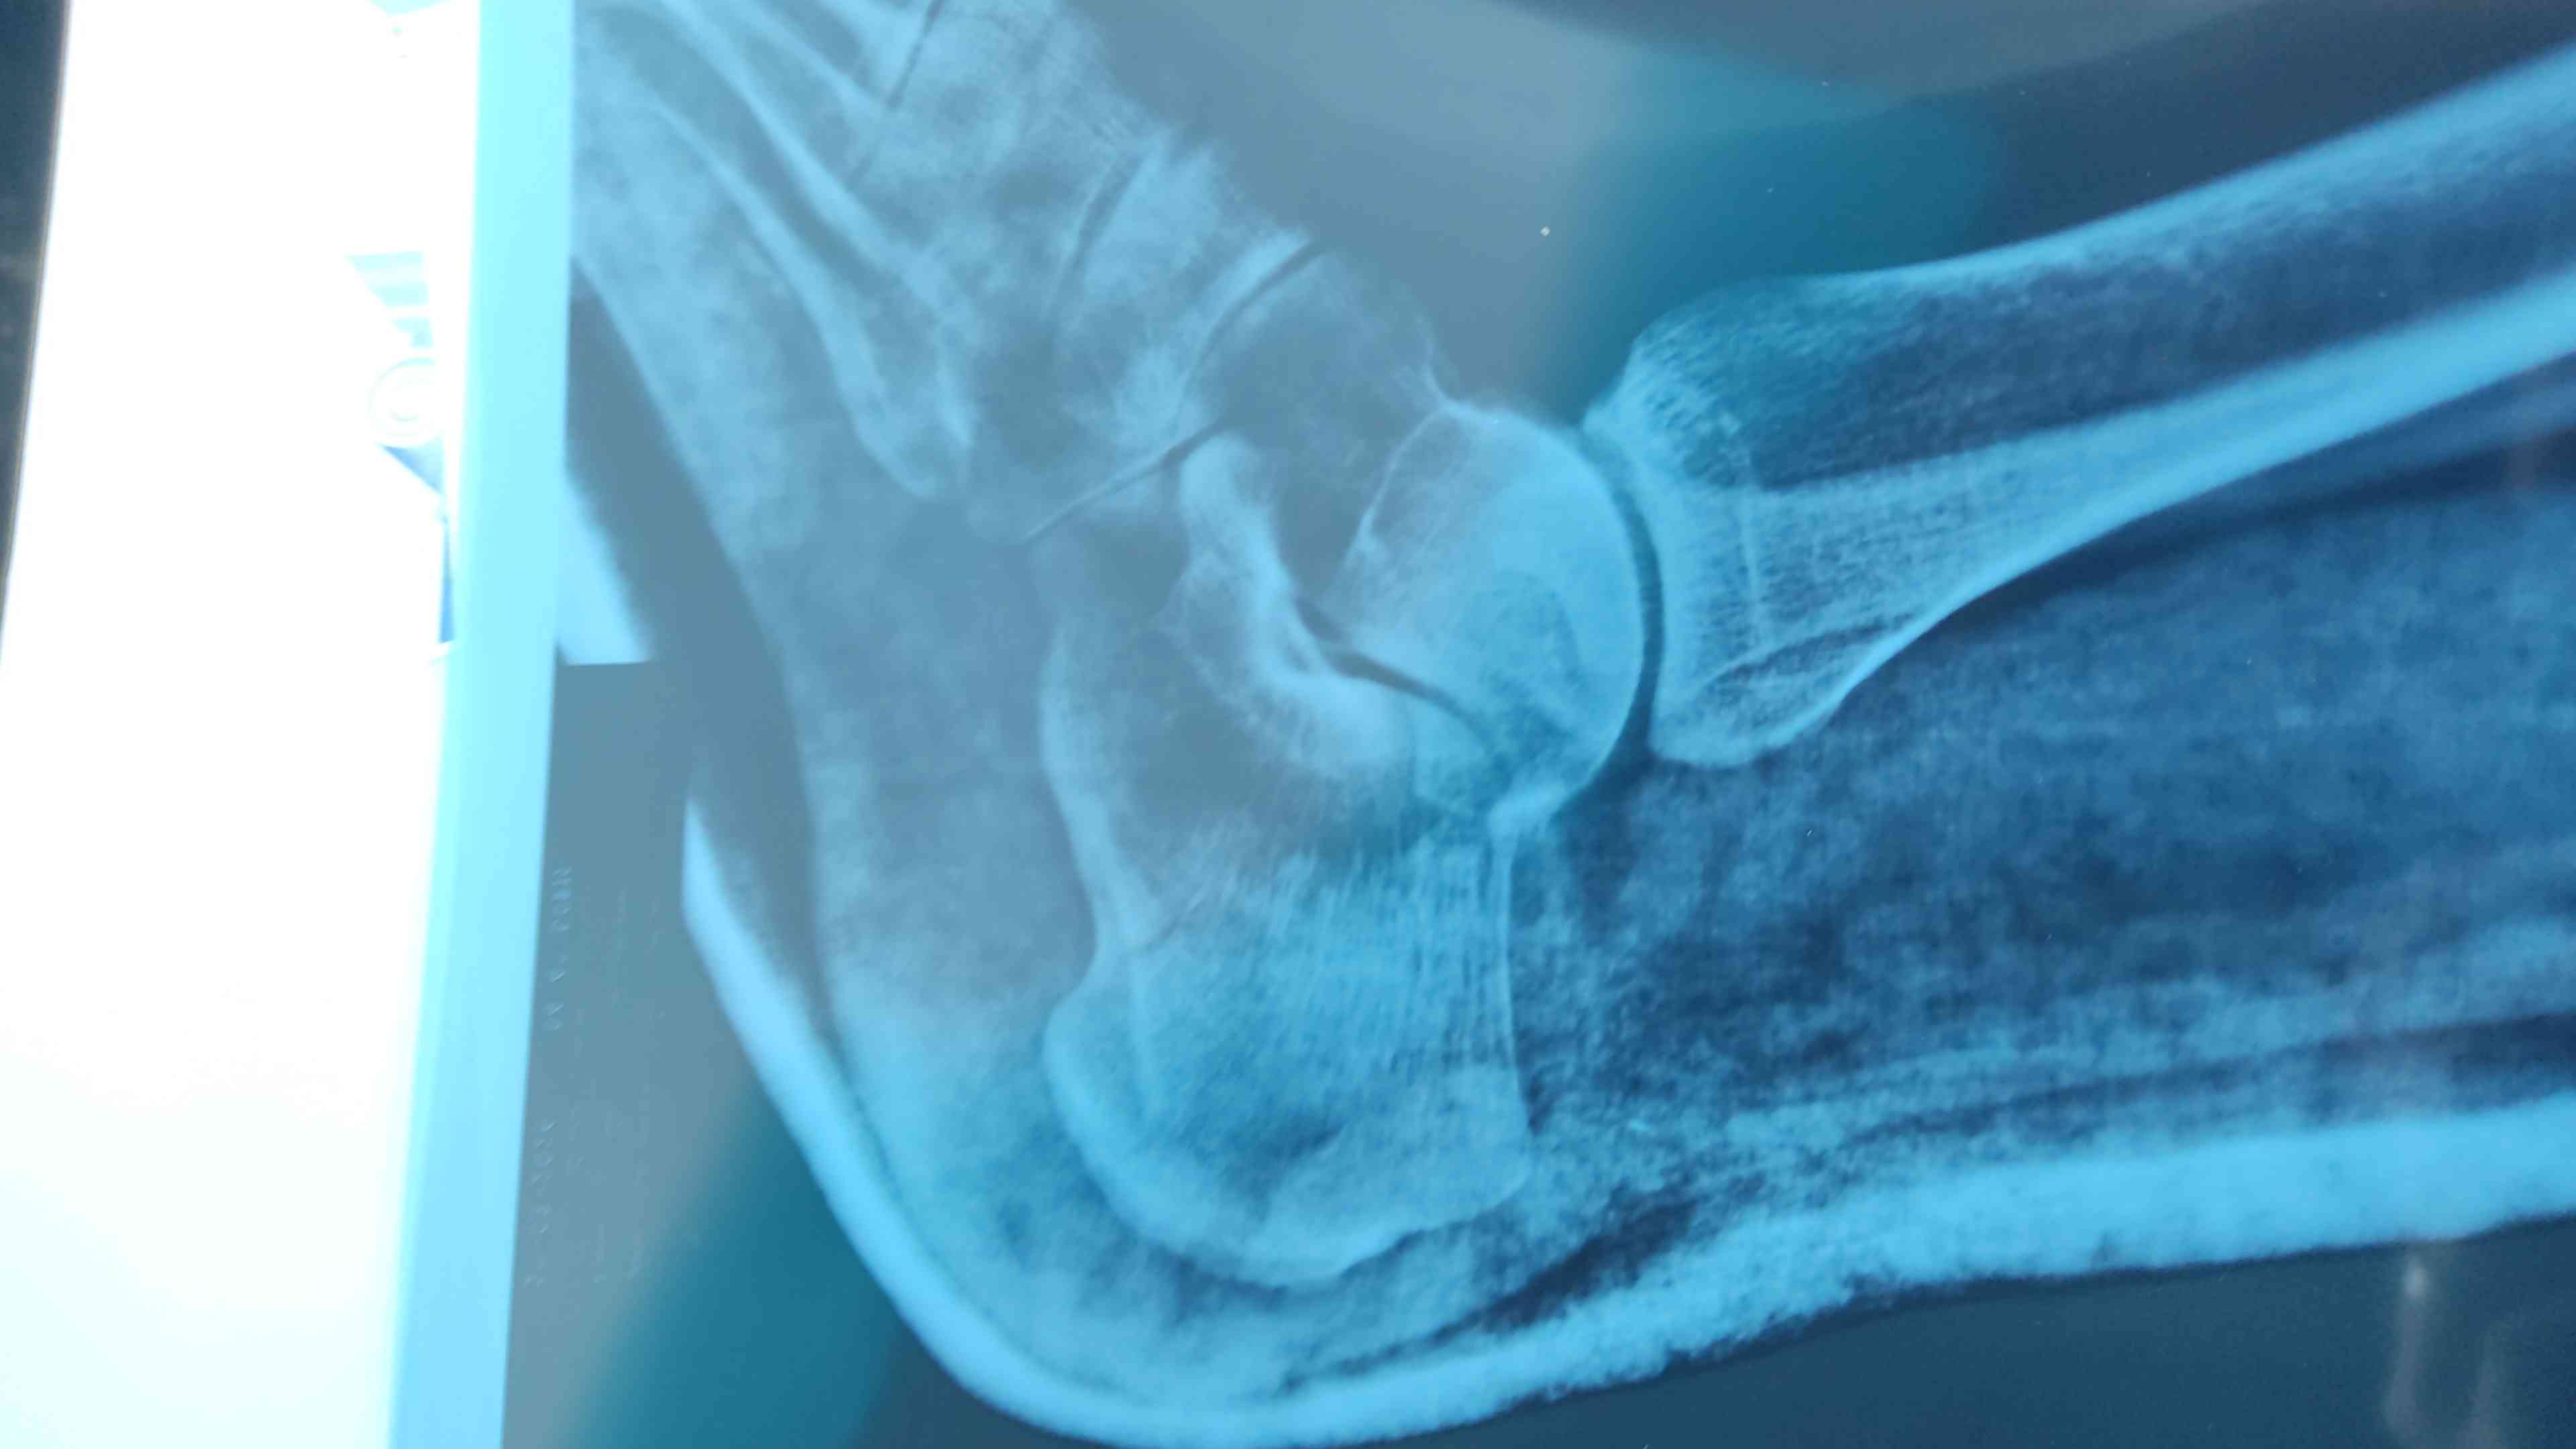

مرحبا قدمي إلتوت تحتي ووقعت مع الم شديد ذهبت للدكتور وصورت شعاعي فقال هناك كسر ليس متبدل وليس هناك ورم لكن يوجد بروز لعظمة الكاحل ذهبت لدكتور اخر قال لايوجد كسر